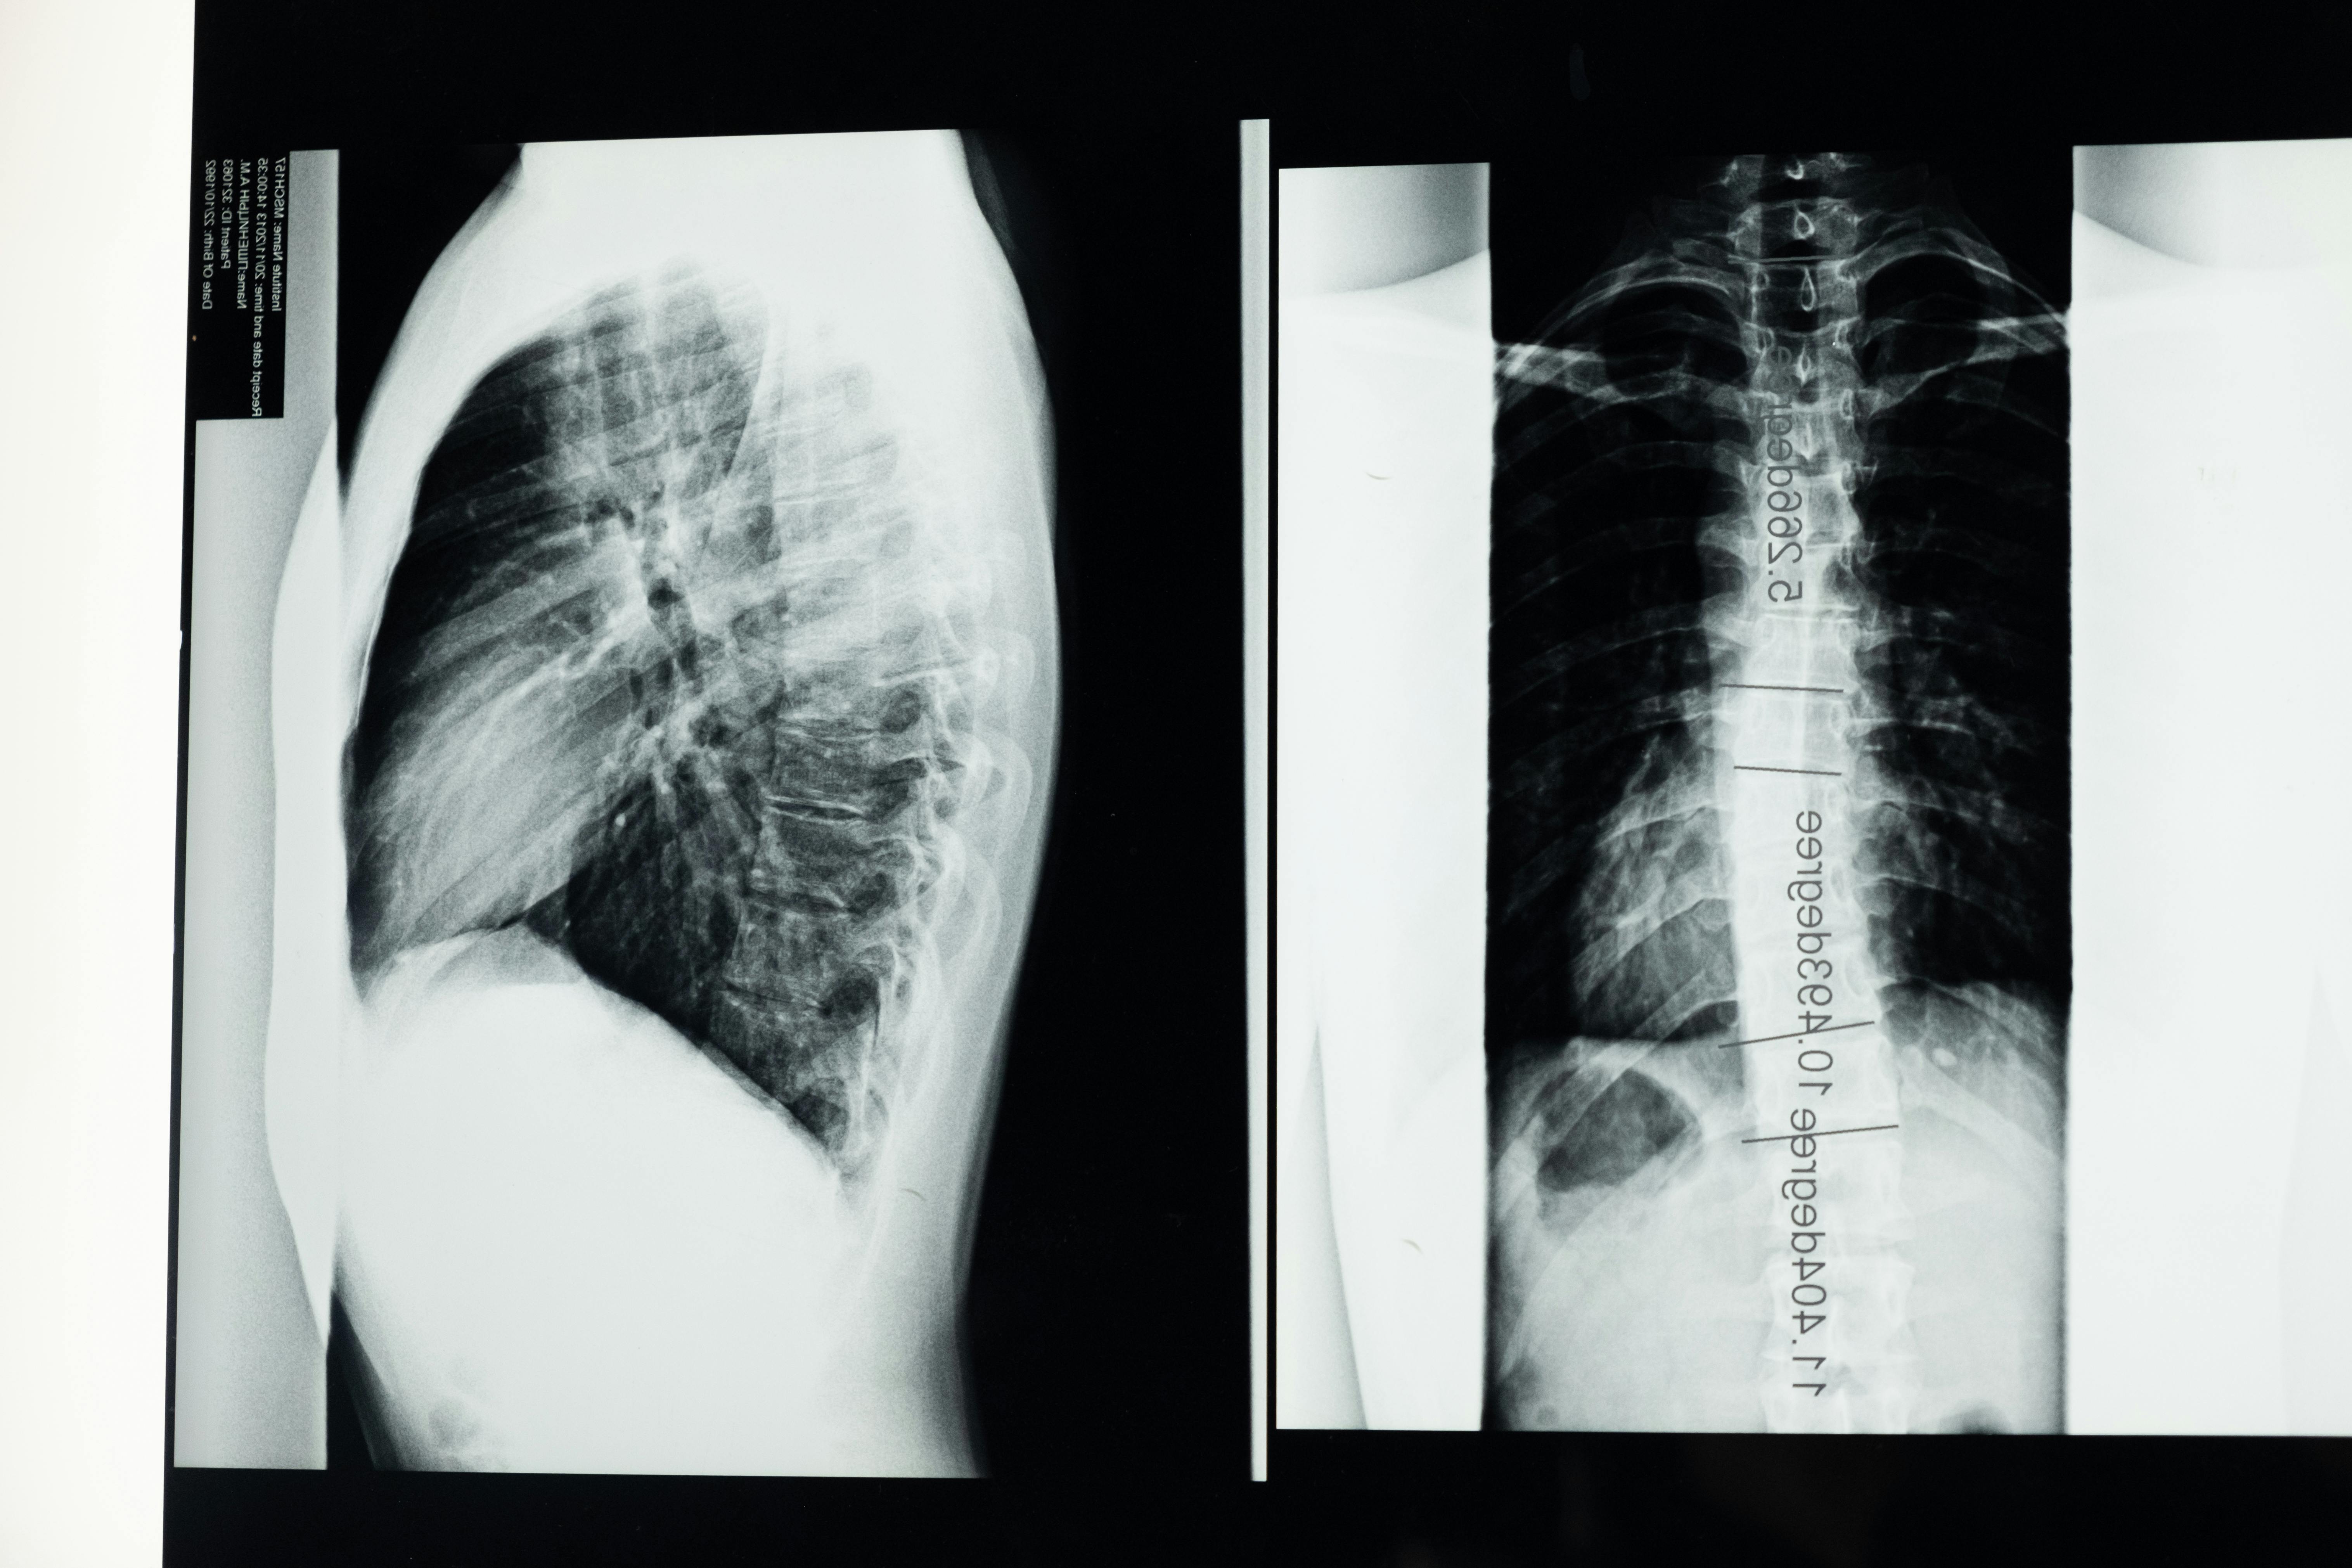

(1) 엑스레이(X-ray) 검사 – 척추가 휘어진 정도(코브 각, Cobb’s angle)를 측정하여 경증, 중등도, 중증을 구분합니다.